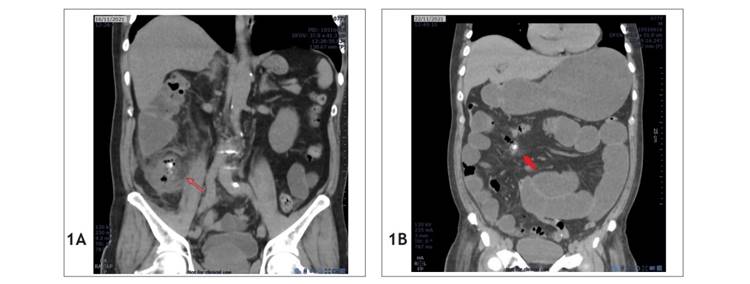

Se trata de una mujer de 23 años que ingresó a emergencia de un hospital público de Lima, Perú, el 17 de octubre del 2022 (día 1), quejándose de dolor tipo cólico en la fosa iliaca derecha que tenía 4 horas de duración; también informó sobre antecedente de cesárea. Los exámenes revelaron sus leucocitos: 9080/mm3; posteriormente, fue diagnosticada de apendicitis aguda por clínica, que se corroboró por una TC (Figura 1A). Ese mismo día se le realizó una apendicectomía laparoscópica, donde se evidenció un apéndice cecal supurado de 7 x 0,9 cm, con líquido purulento de aproximadamente 50 cc de volumen en fondo de saco de Douglas.

En el posoperatorio, la paciente cursó con evolución favorable, y fue dada de alta al día siguiente de la operación (día 2). En el segundo día postoperatorio (día 3), reingresó a emergencia del mismo hospital por presentar dolor en el hipogastrio, náuseas y vómitos. Se le realizó una TC sin contraste que informó de los hallazgos (19 de octubre) (Figura 1B): "impresiona líquido libre en fondo de saco de Douglas y presencia de apendicolito". Leucocitos: 6020/mm3, proteína C reactiva (PCR): 151,44 mg/l.

Figura 1 Tomografías computarizadas del caso 1. (A) Tomografía abdominal preoperatoria, la flecha roja indica el apendicolito. (B) Tomografía abdominal posoperatoria, la flecha roja indica el apendicolito libre.